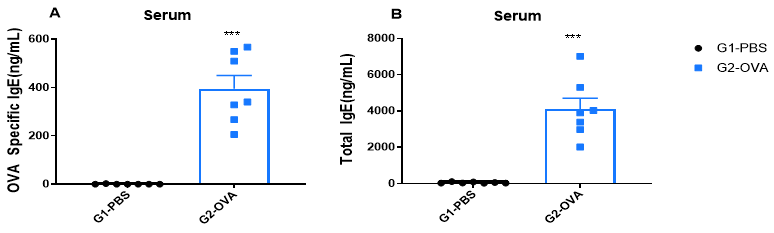

IgE Induction in Serum of Asthmatic Mice

Increased IgE levels in serum of OVA-induced mice compared with controls. Serum was isolated at the end of the experiment and concentrations of OVA-specific IgE (A) and serum total IgE (B) were measured using ELISA.